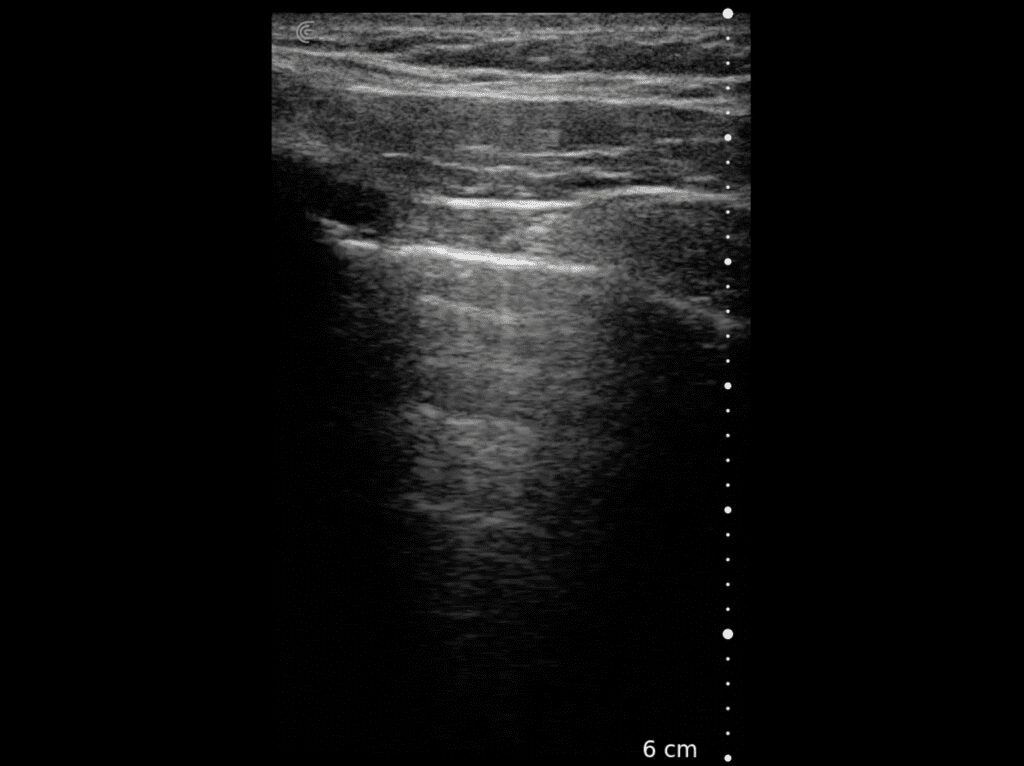

In patients with dyspnea, tachypnea, or hypoxemia, lung ultrasound can help rapidly diagnose the cause. Powered by AI, the Clarius PAL HD3 is commonly used to rapidly perform both shallow and deep lung imaging to effectively rule out pathologies like pneumothorax and pleural effusion. Lung ultrasound has been shown to outperform auscultation and chest radiography in identifying cardiac from non-cardiac causes of dyspnea with significantly higher accuracy and specificity.